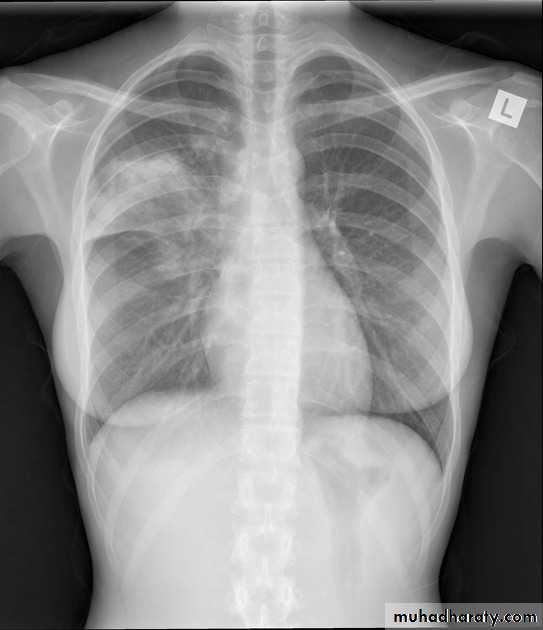

Differentiating the Causes of an Opacified Hemithorax

Atelectasis of an entire lungA large pleural effusion

There is a shift of heart and hemidiaphragm toward side of opacification (toward side of volume loss)Pleural Effusion

It acts like a massPushing the heart and trachea away from the side of opacification

pneumonia

The hemithorax is opaque and there isno shift of the heart or tracheaThere may be an air bronchogram sign present